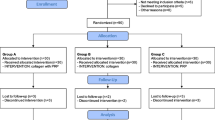

Patients were divided into two groups, the PRP group and the exercise group, in a consecutive order. The PRP group received PRP injection one time while the exercise group followed self-exercise programs for strengthening rotator cuff tendon.

A total of 30 patients were recruited from April 2015 to January 2017. Table 1 shows the initial baseline characteristics of the patients. In the PRP group, three patients were lost to follow-up from 6 weeks after the PRP injection, one patient was lost to follow-up from 12 weeks after the procedure, and four patients were lost to follow-up from 24 weeks after the procedure. In the exercise group, five patients were lost to follow-up from 6 weeks after the PRP injection, two patients were lost to follow-up from 12 weeks after the procedure, and no patients were lost to follow-up from 24 weeks after the procedure. Lost data was managed by the worst-case imputation method. Among patients lost to follow-up in the PRP group, one patient paradoxically increased their pain after PRP injection and was diagnosed as having newly developed adhesive capsulitis. Exercise compliance in the exercise group was 90.8 ± 30.6% at 6 weeks, 94.2 ± 37.4% at 12 weeks, and 87.4 ± 39.0% at 24 weeks.